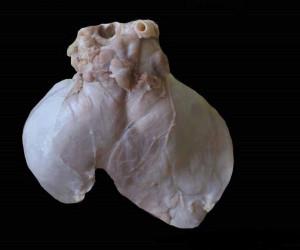

Savez-vous ce que représente cette image ?

Je vous donne un indice : ce petit organe de 2 centimètres se cache dans la partie supérieure de votre thorax, entre les poumons, sous le sternum et au-dessus du cœur.

Il est essentiel au corps humain, en particulier sur le plan immunitaire.

Son nom est le thymus !